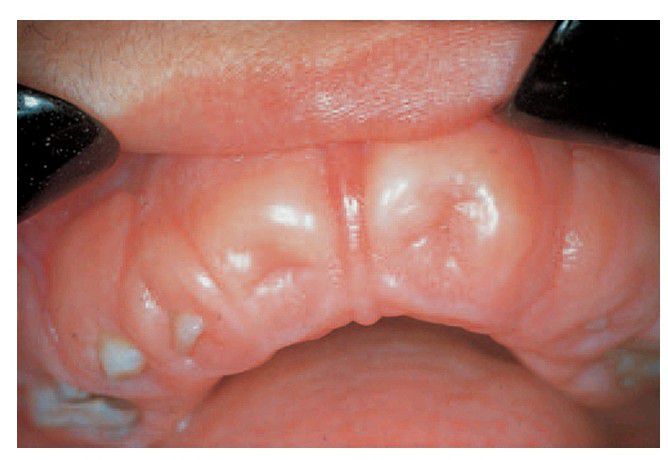

Hereditary gingival fibromatosis

. Fibrous overgrowth of the gingiva has covered the crowns of the teeth and almost buried them (pseudo-anodontia).